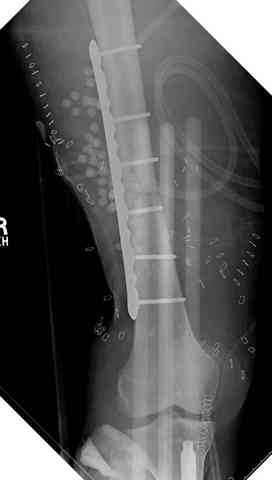

Может, данное наблюдение поможет в принятии решений в подобных ситуациях.

Огнестрельный дефект костей и передней группы мышц, поступил с юнилатеральным аппаратом, стабильность плохая, из раны обильное гнойное

отделяемое. #1;#2. Стержневой апп. снят, наложен апп. Илизарова, дренажно-ирригационная система промывки раны. #3; #4. После стихания инфекции,

аппаратом постепенно создана рекурвация для сближения контактов мышц (сухожилий) передней группы голени. #5;#6. Наложен шов на сухожлилия М.

Tibialis anterior и M extensor digitorum L. Одновременно компактотомия костей голени в В/3 для замешение дефекта костей. #7;#8. Постепенно

исправлена ось и возмещен дефект. В результате восстановление тыльной флекcии стопы и функции конечности. #9;#10;#11